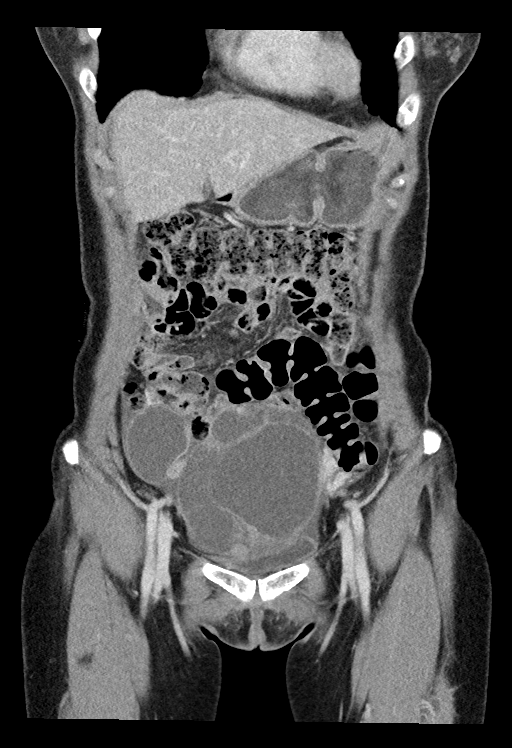

- 실제 예시

- CT 이미지(원천:PNG – 라벨링:JSON)

| 원천데이터 | 라벨링데이터 |

|---|---|

![]() |